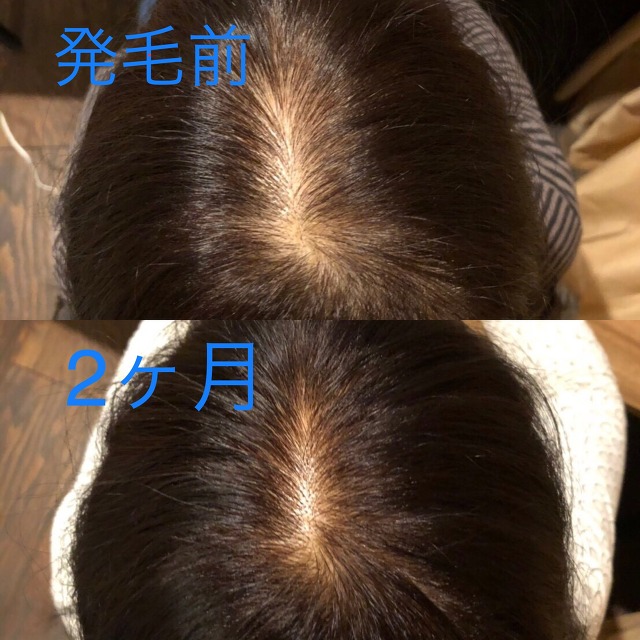

★発毛・薄毛部門からのお知らせ★

⚡薄毛・育毛にお困りの方に朗報です⚡

☑市販の育毛剤じゃ効果が出ない

☑抜け毛が気になってきた

☑全体的に髪のボリュームがなくなってきた

☑親族に薄毛の方がいる

こんな方はぜひご相談ください!

悩んでいる時間がもったいない!

確実に満足のいく結果を出します!

「受けてみたいけど…踏ん切りがつかない」という方もいらっしゃると思います。

嬉しいお知らせ!初回のカウンセリングは無料です。

完全予約制なので貸切でご相談いただけますので内容を聞かれる心配もなし!

それでもまだ迷ってる方は、もう少し迷われていて下さい。

あなたの決心がつくまで私は見捨てません。

あなたにとって「人生最後の発毛治療」にしましょう。

本気で私もあなたと向き合います!

「発毛のカウンセリングをお願い!」とご連絡下さい。